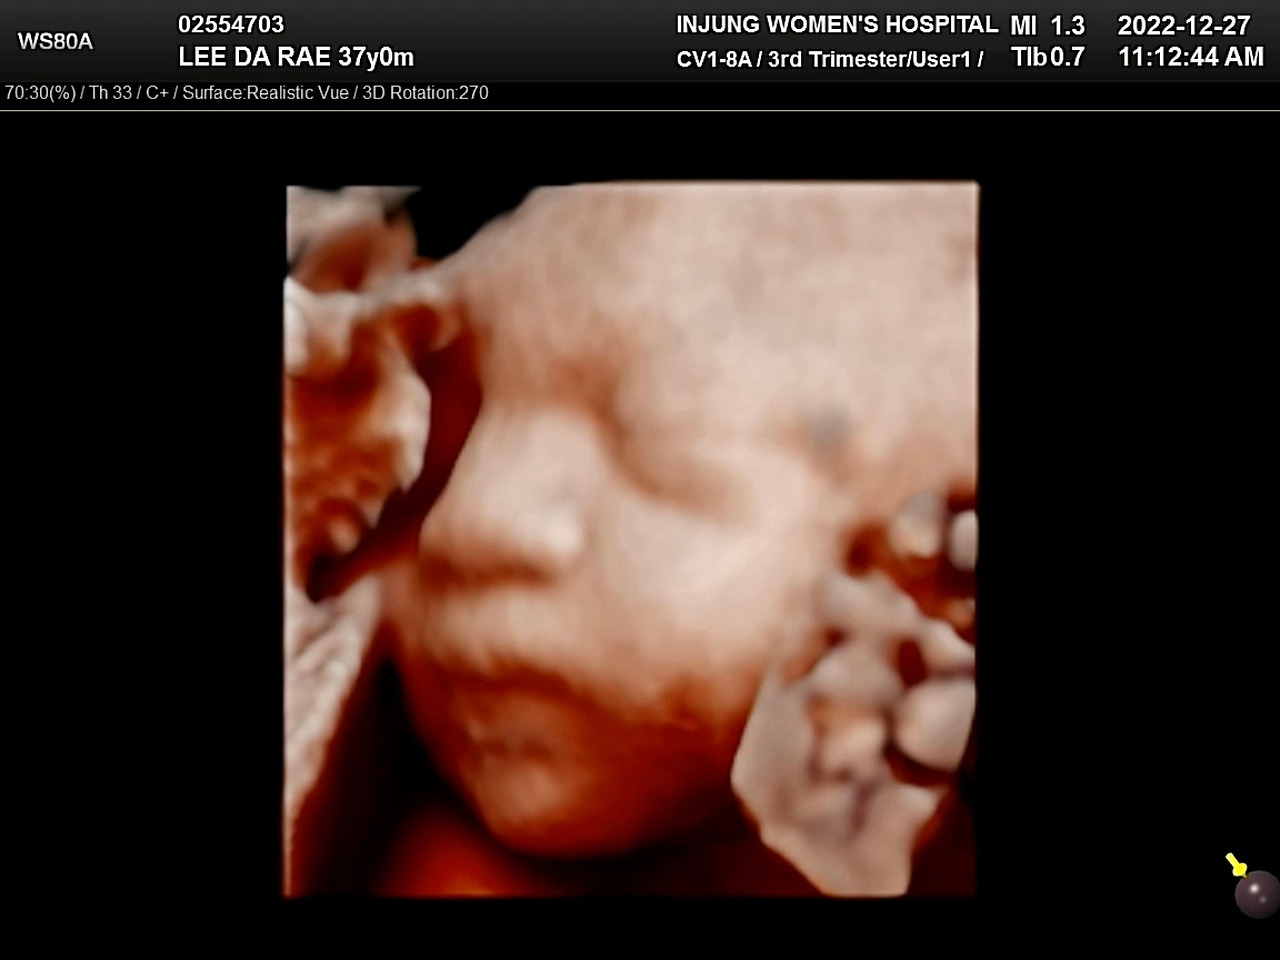

포도 입체초음파

지금껏 산부인과 검진은 늘 혼자 갔는데, 26주 검진에는 시간이 맞아 온 가족이 함께 병원에 갔다. 혼자 가는 것도 싫진 않았지만, 남편과 같이 온 산모들을 보면 괜히 부러운 마음이 들었던 터라 같이 병원에 가는 길이 신이 났다. 입체초음파를 했는데, 포도의 얼굴이 아인이가 뱃속에 있었을 때 얼굴과 묘하게 닮았다. 초음파실에서 나와 아인이에게 포도가 아인이랑 닮았다고 했더니, 정색을 한다. 남편은 옆에서 아인이가 초음파 화면을 보는 걸 어지러워했다면서 아인이를 챙기기 바빴다. 역시 내 예상대로 움직여주지 않는 황씨들. 어쨌든 포도는 넘 귀엽다. 얼굴 잘 보여줘서 고마워!